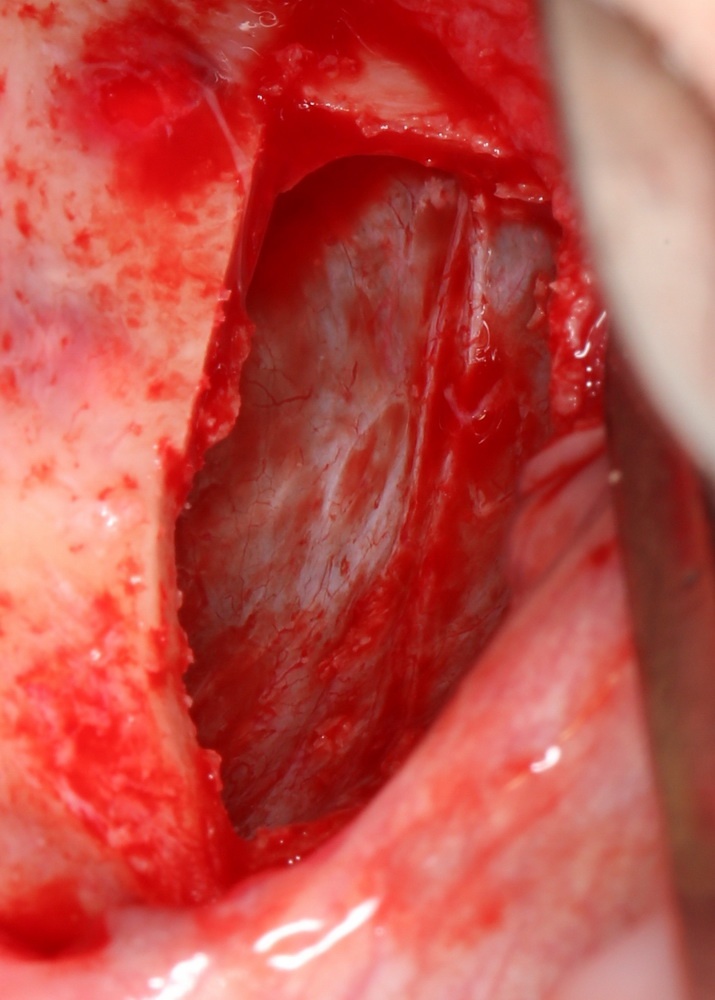

Самый известный способ проверить, есть ли повреждения слизистой оболочки верхнечелюстной пазухи — это попросить пациента глубоко вдохнуть и выдохнуть. При этом, шнайдерова мембрана будет двигаться:

На вдохе втягиваться внутрь:

На выдохе — выпирать:

Если она не двигается, если из субантральной полости идут пузыри — это верный признак, что где-то слизистая оболочка повреждена.

Однако, данный тест не дает гарантии, что перфорации нет. Небольшая перфорация может быстро закрыться кровяным сгустком, у пациента может быть просто заложен нос и т. д. — поэтому полностью полагаться на него нельзя.